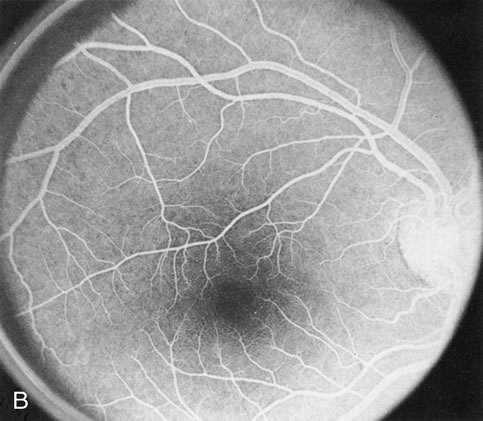

STARGARDT'S DISEASE (FUNDUS FLAVIMACULATUS)

In Stargardt's disease, thes most common hereditary macular dystrophy, FA has a variety of functions. In the mildest fundus presentation, with visual symptoms and visual function out of proportion to the observed maculopathy, FA can confirm or even make the diagnosis and can avoid a mistaken diagnosis of malingering, hysteria, or central nervous system disease (Fig. 9A and B). When a maculopathy is present without surrounding parafoval flecks, FA may show patchy areas of transmission hyperfluorescence in the posterior pole, indicating a more diffuse involvement (Fig. 9C and D).

Fig. 9. Stargardt's disease–fundus flavimaculatus. The mild maculopathy (without parafoveal flecks) (A) is confirmed by the angiogram (B). The relative absence of the underlying choroidal flush, resulting in an easier visualization of the overlying retinal capillary circulation, has been referred to as the “silent” or “dark” choroid, and is considered a common finding in this disease. The diagnosis is confirmed in an individual with a pigmentary maculopathy without flecks (C). Here the angiogram demonstrates widespread transmission hyperfluorescence and a “silent” or “dark” peripapillary area (D). When the posterior pole shows multiple yellowish-white flecks (E), the angiographic findings do not necessarily correspond to the flecks (F). It should also be noted that despite the widespread abnormalities, the background choroidal fluorescence is normal.

In a large majority of patients (86% in one study),20 there is an absence or decrease in the background choroidal fluorescence (which is referred to as the “silent” or “dark” choroid) (see Fig. 9B). This warrants special attention because it occurs so frequently, is rarely found in other retinal disorders,21 and may be related to histopathology that shows an increase in lipofuscin in the RPE.22